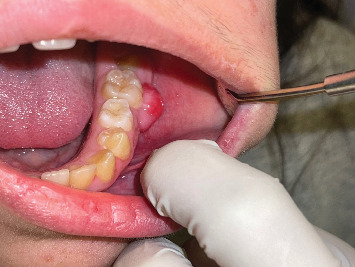

绒毛瘤是一种具有正常组织学的组织块,类似于身体的一部分,但与它所在的部分不同。它不同于错构瘤组的病理是正常组织,但杂乱无章,发现在一个异常的位置。在口腔发生骨性脉络瘤病变的文献很少,大多数病例已报道在舌头。很少发生在牙间龈。事实上,虽然有许多老年人的病例报道,但脉络膜瘤被认为是一种发育异常,涉及年轻人。鉴别诊断包括软骨化生、多形性腺瘤、唾液腺组织,以及可能导致口腔错构瘤的炎症或创伤性病变。在这个病例报告中,我们提出了一个病例骨性脉络瘤起源于下颌,后颊龈在一个年轻的女性患者。

Choristoma is a mass of tissue with normal histology similar to a part of the body that is different from the one in which it is located. It differs from the hamartomatous group of pathology which is normal tissue, but disorganized, found in an abnormal location. Documentation of the occurrence of osseous choristoma lesions in the oral cavity has been scarce, and most of the cases have been reported in the tongue. It is very seldom to arise from the interdental gingiva. Indeed, choristoma is considered a developmental anomaly, involving younger individuals, although many cases among older adults have been reported. The differential diagnoses include cartilaginous metaplasia, pleomorphic adenoma, salivary gland tissue, and the lesions of inflammatory or traumatic origin that may give rise to hamartomas in the oral cavity. In this case report, we present a case of osseous choristoma arising from the mandibular, posterior buccal gingiva in a young female patient.